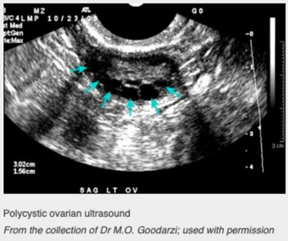

Imaging- PELVIC USS:

* Polycystic ovaries present in 75% of women with PCOS but also seen in up to 25% of normal women

* TVUSS gives higher resolution images than transabdominal

* Will see 12 or more follicles or increased ovarian volume >10cm3

* Can also assess endometrial thickness (should be done after first withdrawal bleed in women starting progestogens)

* Follicles may be arranged around the periphery of the ovary, giving a string of pearls appearance